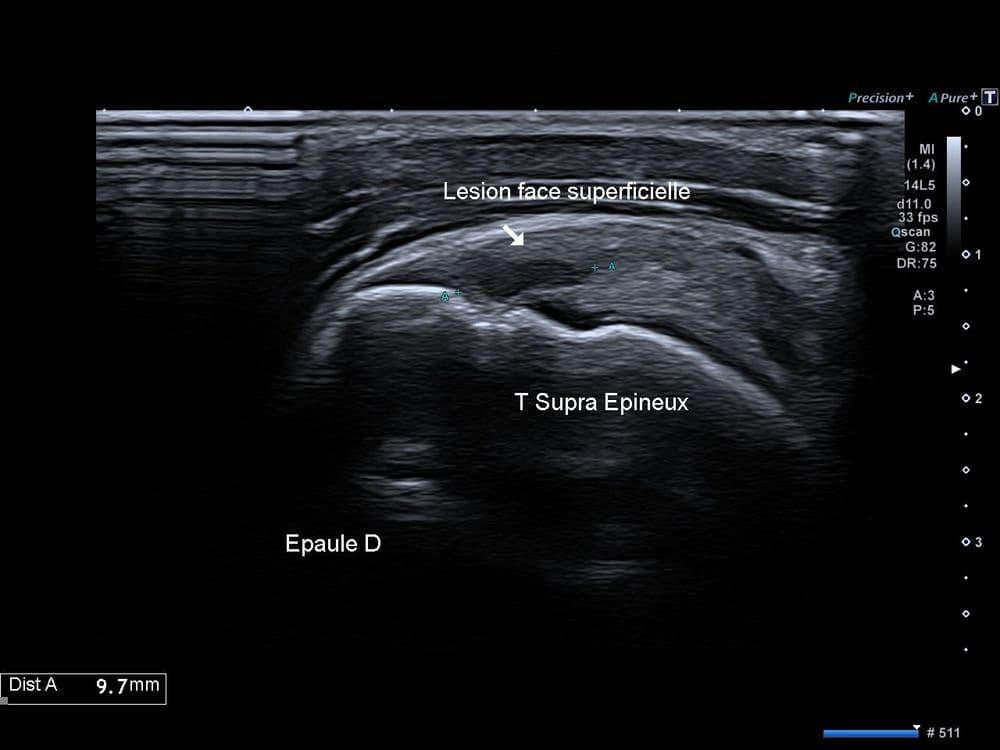

Scapulalgie droite non traumatique en lien avec une lésion dégénérative partielle de la coiffe des rotateurs.

US